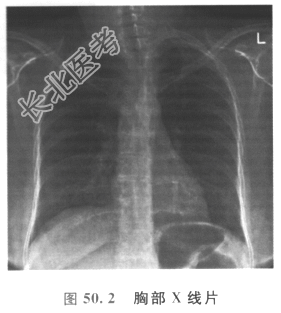

胸部X线片如图50.2所示